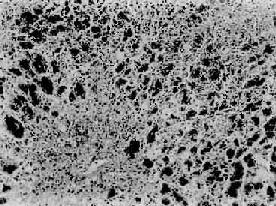

本型病变可见肝细胞坏死严重而广泛。肝索解离,肝细胞溶解,出现弥漫性的大片坏死。坏死多自小叶中央开始,向四周扩延,仅小叶周边部残留少数变性的肝细胞。肝窦明显扩张充血并出血,Kupffer细胞增生肥大,并吞噬细胞碎屑及色素。小叶内及汇管区有淋巴细胞和巨噬细胞为主的炎性细胞浸润(图10-40)。残留的肝细胞再生现象不明显。肉眼观,肝体积显著缩小,尤以左叶为甚,重量减至600~800g,质地柔软,表面被膜皱缩(图10-41)。切面呈黄色或红褐色,有的区域呈红黄相间的斑纹状,故又称急性黄色肝萎缩或急性红色肝萎缩。

急性重型肝炎

图10-40 急性重型肝炎

肝细胞大片坏死消失,小叶中心部最重,周边部残存的肝细胞变性。坏死区有炎性细胞浸润